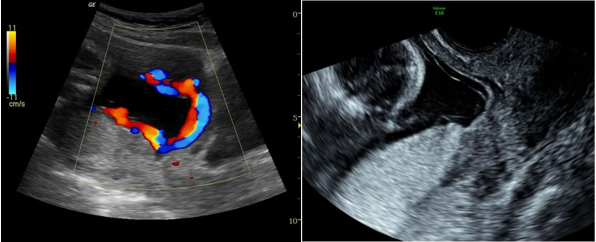

9. BÁO CÁO TRƯỜNG HỢP CHẨN ĐOÁN VÀ XỬ TRÍ THÀNH CÔNG CASE MẠCH MÁU TIỀN ĐẠO TẠI BVĐK TỈNH QUẢNG TRỊThai phụ HTML 28 tuổi mang thai lần 1, 39 tuần. Quá trình khám thai phát hiện dây rốn bám màng mép dưới bánh nhau. Vào viện vì có dấu hiệu chuyển dạ. Ghi nhận lúc vào viện cổ tử cung hở, tử cung gò 1/10 phút. Qua siêu âm ghi nhận 01 thai tương ứng 39 tuần, dây rốn bám màng. Khoa Phụ Sản tiến hành siêu âm Doppler qua đầu dò âm đạo phát hiện mạch máu tiền đạo. Thai phụ được tiến hành mổ lấy thai cấp cứu. Sau mổ đón ra 01 bé trainặng 3800 gr. Trong mổ phát hiện mạch máu tiền đạo. Sau mổ an toàn kiểm tra bánh nhau xác định dây rốn bám màng mạch máu tiền đạo. Sau đó thai phụ được thực hiện da kề da cho em bé. Sau 4 ngày điều trị thai phụ và trẻ sơ sinh xuất viện khỏe mạnh.